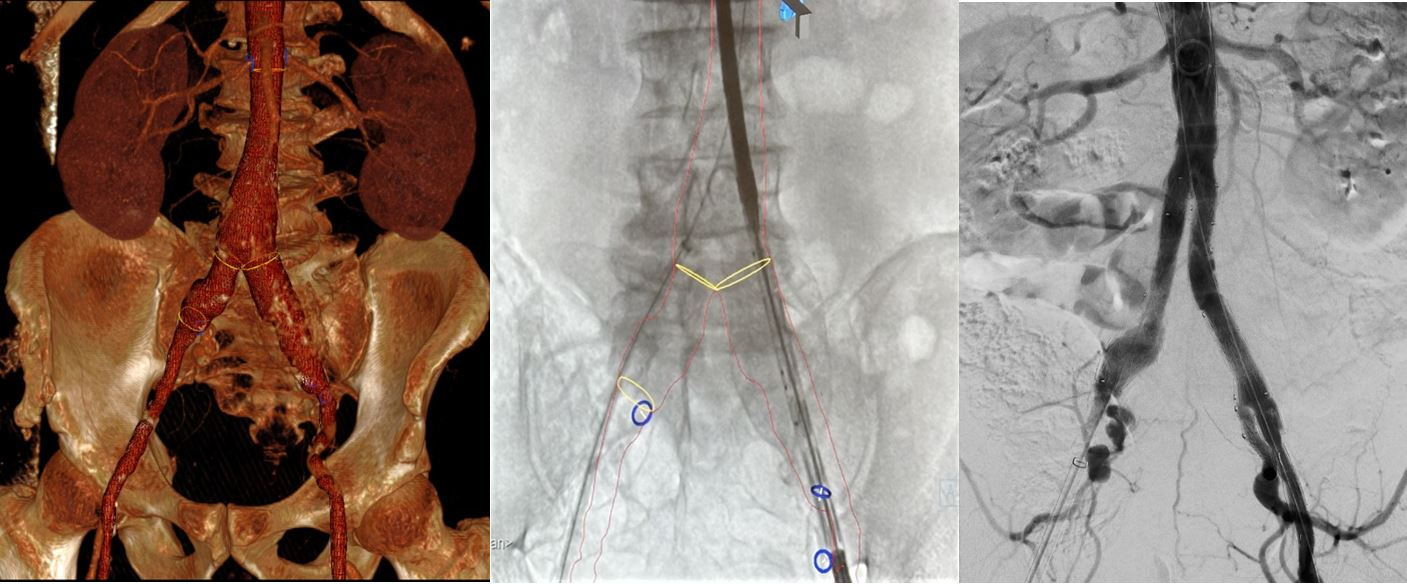

Pacient s výduťou brušnej aorty a panvových tepien ošetrený miniinvazívne cez malý rez v slabine pomocou špeciálnej cievnej protézy, ktorá umožňuje zachovať tok aj do vnútornej panvovej tepny. Pomocou 3D navigácie a fúzie s CT obrazom sa skrátil celkový čas implantácie a výrazne zredukovala radiačná dávka aj objem podanej kontrastnej látky.